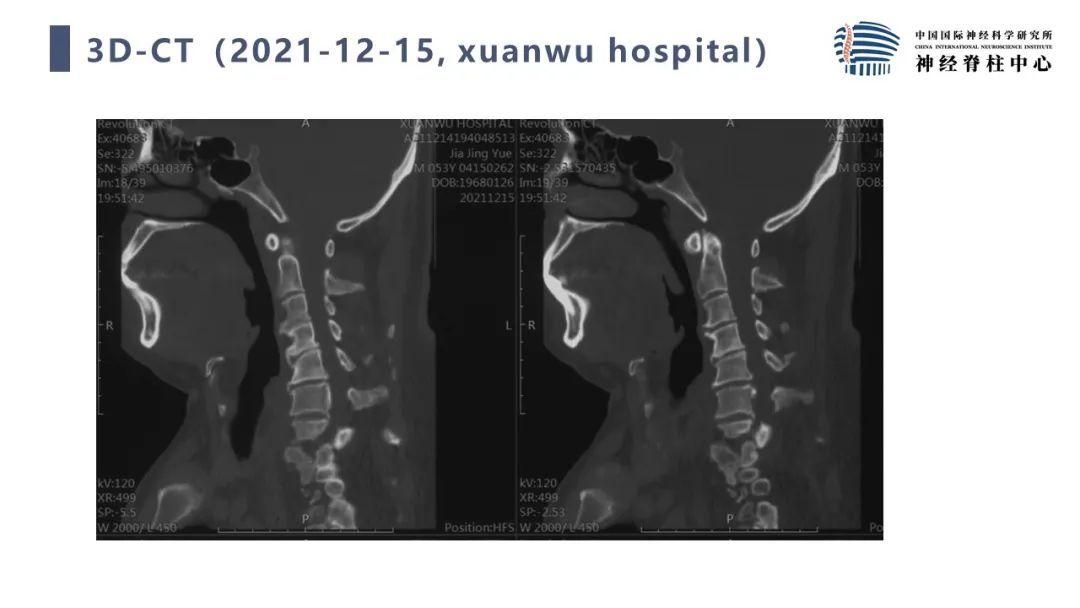

段婉茹副主任医师:脊髓栓系的治疗

首都医科大学宣武医院